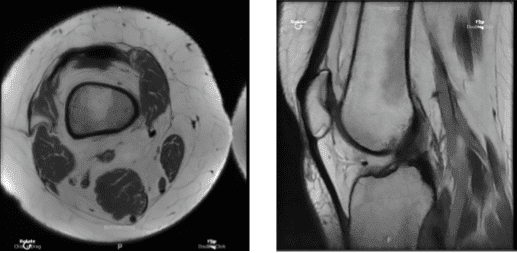

MRI Right knee non-contrast

After being involved in a car accident, a 46-year-old female patient came to visit a doctor at the office and complained of pain on the inside of her right knee. Her conventional medical care failed. A vertical radial tear of the medial meniscus of the right knee was discovered by MRI.

An examination of the medial tibiofemoral compartment revealed a vertical radial tear along the body of the medial meniscus that extended up to the capsule. The intercondylar notch examination revealed an undamaged ACL.